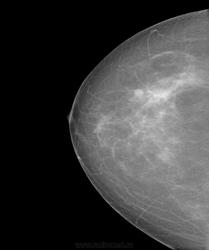

Возраст женщины за 55лет.

Жалоб нет. С целью профилактики самостоятельно  прошла обследование.

В общем пахнет мастэктомией.